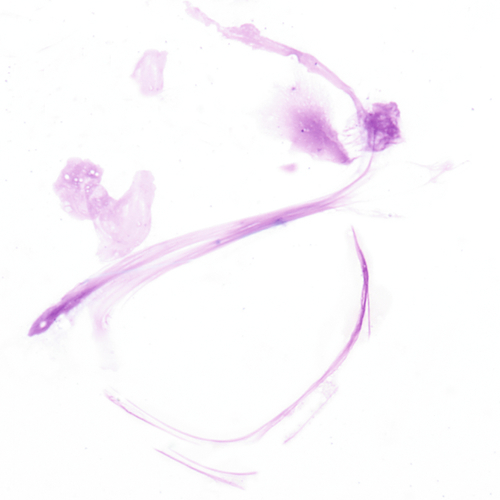

The specimen in Figure 24–39 is from a patient who experienced head trauma.

Fibers from the filter paper may appear near the edges of the slide. Fibers may be birefringent but lack the sharp pointed ends of monosodium urate crystals.